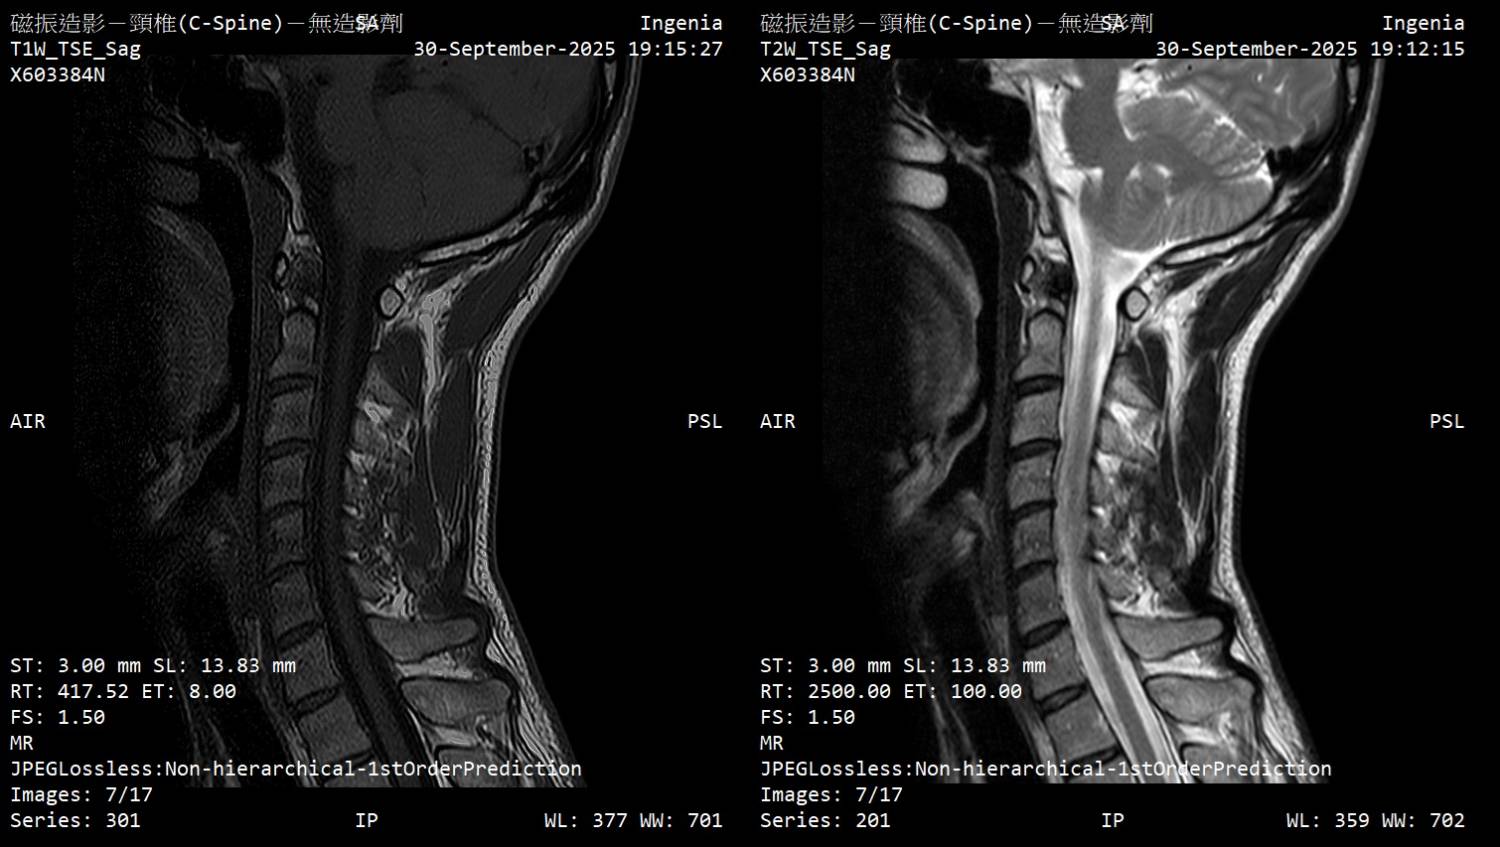

大家好 因为下列症状从2月开始断续发生,8月运动伸展上背後症状加剧 前往神经内科、神经外科就诊,目前不知道下步该往什麽方向? 该矫正姿势(脖前倾)? 复健科拉脖子? 寻求其他意见? 再观察? 症状 - 起床双手握不紧的感觉,白天正常 - 双手指尖感觉迟钝、左手臂外侧微麻感 - 双脚底有微微电流感(静止才感觉得到)、肌肉不定时抽动感、右小腿肚微麻 - 近半年有两次躺着以为有地震,结果没有震 检查 - 霍夫曼测试阳性、双膝反射增强 - 动作诱发电位正常、感觉诱发电位颈到手异常 11.3ms (标准<11ms) - 上肢神经传导正常 (一家正常/一家右正中神经异常) - 下肢神经传导左小腿/脚背异常 (以前受伤後遗症) 诊断 - 神内医师:颈椎有压迫、C5-C6黄韧带增生,建议先复健看看 - 神外医师:没有问题,应该是双手腕隧道症候群 颈椎MRI (全部) https://drive.google.com/drive/folders/1AmMB51gjrYYUIF8by9BEnTz1ahY3hbVp 文字报告 Unremarkable curvature of cervical spine No obvious herniated disc No obvious neuroforaman stenosis Suggest correlate clinical data. IMP: Unremarkable finding 神内医师判断可能压迫的部份 https://i.meee.com.tw/0E4JmY7.jpg

https://i.meee.com.tw/t3QgaWs.jpg

https://i.meee.com.tw/CsUmHf3.jpg

https://i.meee.com.tw/0C6bI5t.jpg